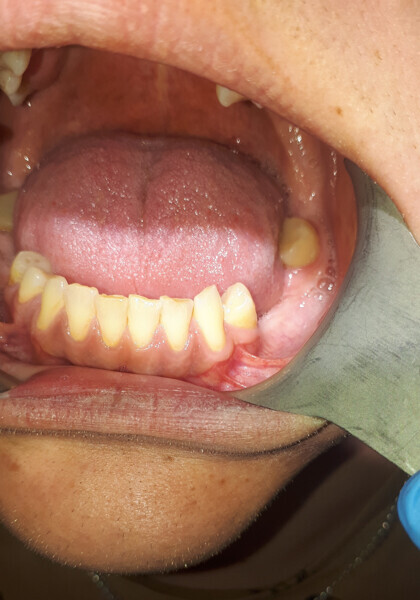

Śródkostna postać torbieli naskórkowej zlokalizowana w żuchwie – opis przypadku